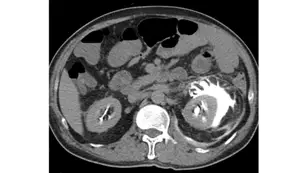

本題主要測驗放射師對於**腹部電腦斷層延遲相(Delayed phase / Excretory phase)的影像判讀,以及泌尿道系統破裂與尿液外漏(Urine extravasation / Urinoma)**的典型影像特徵。

- 造影相(Phase)判定:這是一張腹部無花果軸切面(Axial)電腦斷層影像,位於雙側腎臟水平。可以觀察到雙側腎臟的集尿系統(腎盂與腎盞)內皆充滿了高密度的顯影劑。這表示此影像是在靜脈注射顯影劑後的一段時間(通常為 5-15 分鐘)所擷取,屬於延遲相(Delayed phase)或排泄相(Excretory phase)。

- 正常構造:右側腎臟(影像左側)的顯影劑正常地侷限在腎盂與腎盞系統內。

- 病灶特徵:左側腎臟(影像右側)周圍的**腎周隙(Perirenal space,位於 Gerota's fascia 內)**出現了大量且明顯的高密度液體積聚。由於其密度與腎盂內的含顯影劑尿液相同,這代表含有顯影劑的尿液已經從左側泌尿系統(可能是腎盂或腎盞穹窿)破裂處漏出,積聚在腎臟周圍。